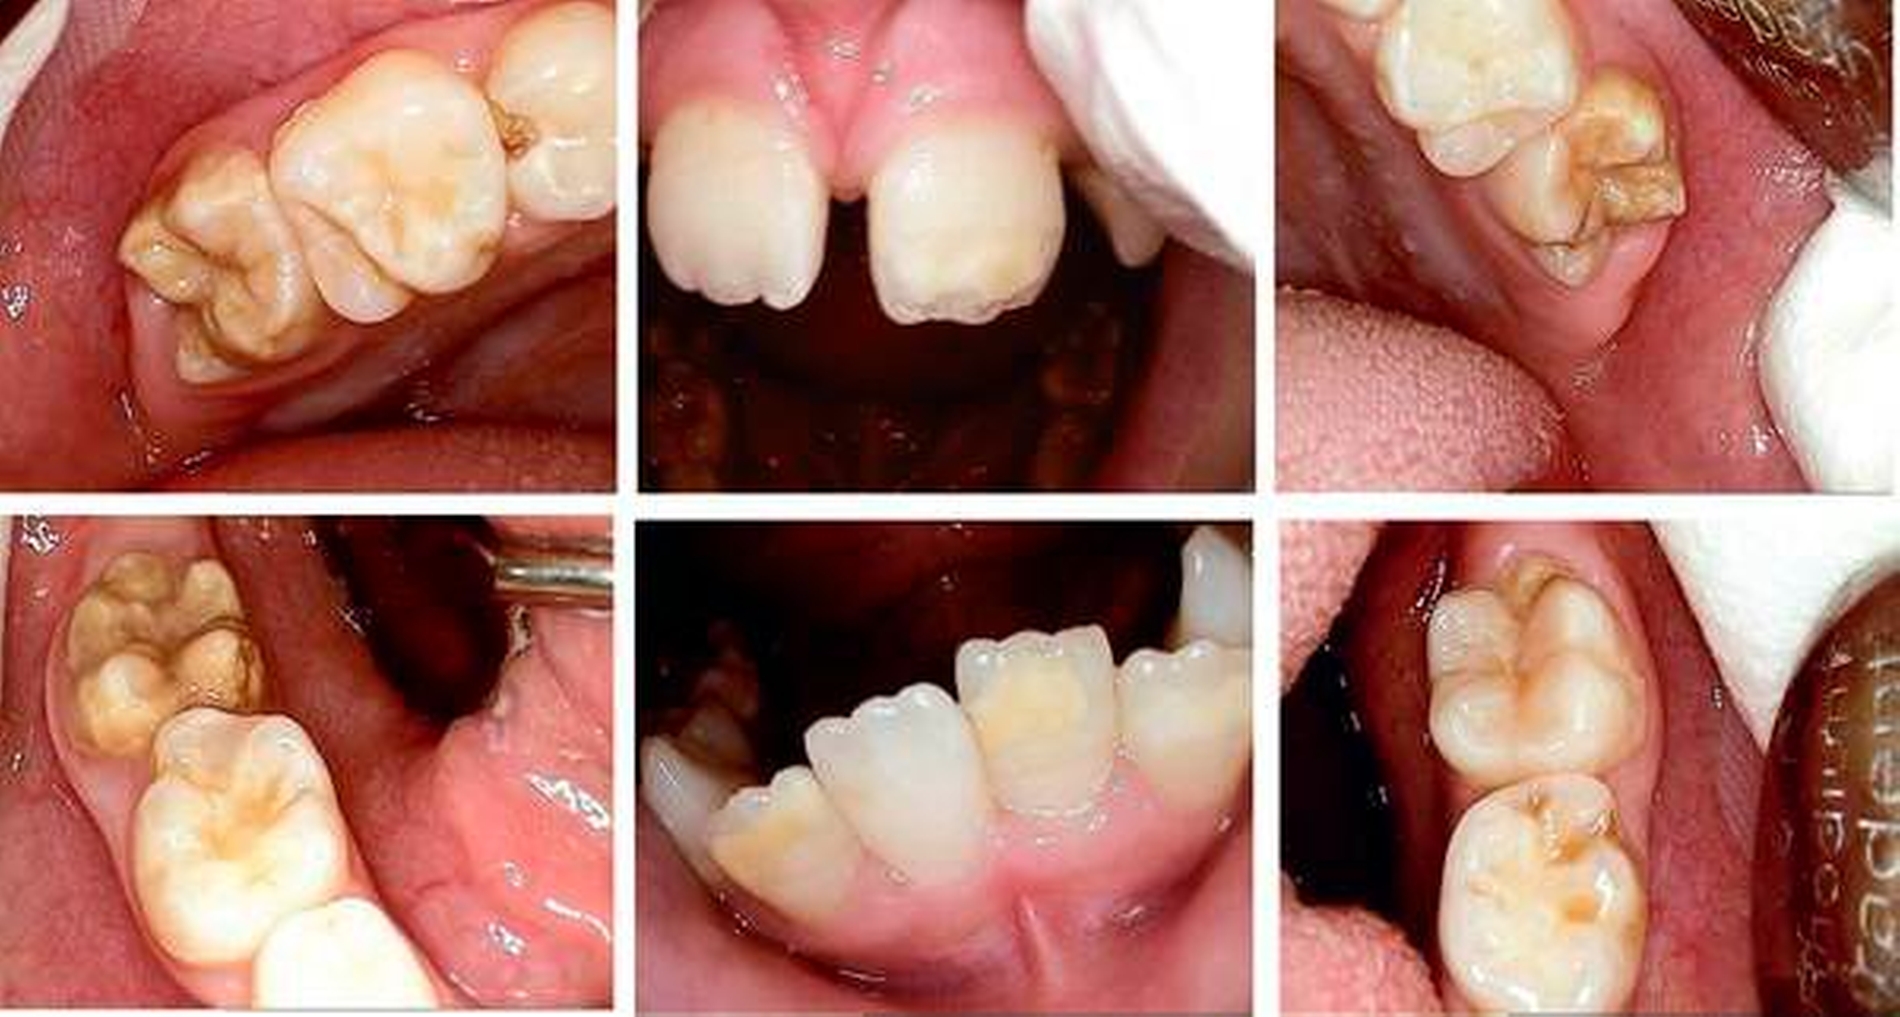

Ausgangsbefund:Während der extraorale Befund unauffällig war, zeigte der intraorale Befund ein kariöses Milchgebiss (Abbildungen 1 und 2).

Behandlungsphase im ZFZ:Im Juni 2008 fand die Milchzahnsanierung in ITN statt. Dabei wurden die Füllungstherapie sowie eine Pulpotomie durchgeführt. Anschließend wurde der Patient zur regelmäßigen Kontrolle und Intensivprophylaxe wieder an den Hauszahnarzt zurücküberwiesen.

Zweiter Befund nach drei Jahren:Im April 2011 stellte sich der Patient erneut im ZFZ vor. Mittlerweile war der Patient sieben Jahre alt und im beginnenden Wechselgebiss zeigten sich Schmelzhypoplasien der Sechsjahresmolaren (Abbildungen 3 bis 5). Da die Zähne starke Empfindlichkeiten und zunehmende Substanzverluste trotz versuchter Fissurenversiegelungen aufwiesen, hat der Hauszahnarzt mit den Eltern entschieden, diese weiter versorgen zu lassen. Somit wurde der Patient wieder ans ZFZ überwiesen zur erneuten ITN-Behandlung.